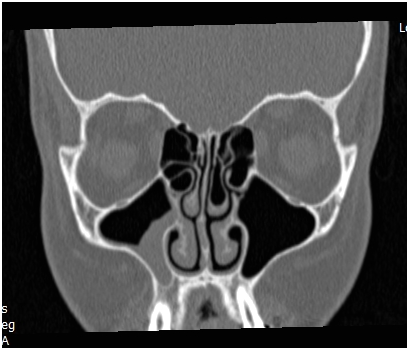

All these classifications are of value in the complex disease pathogenesis and prognosis understanding, but they don’t reflect on the disease extension and surgical steps and so don’t help in the preoperative planning, estimation of the duration of surgery or prediction of surgery related complications. For example, FESS is the term of procedure used to describe surgical management of a case with nasal polyposis and pansinusitis and it’s the same term used to describe surgical treatment of a case with unilateral maxillary sinusitis Figure 1. It is obvious that the first procedure has more serious complications, requires different instruments and experience, and indeed needs longer surgical and anesthesia time.

The increased costs of health service worldwide and providing a stander clinical quality require having obvious plan and protocol for any medical procedure. In our practice we divide FESS into compartments. When we approach the frontal sinus to treat frontal sinus pathology this will be the superior compartment, whereas treating maxillary disorders is the inferior compartment of FESS, (Figure 1). The anterior and posterior compartments are used to describe resection of diseased ethmoid cells and opening sphenoid sinus respectively.

Figure 1 CT scan for patient with unilateral maxillary sinus opacification demonstrating the Inferior compartment of FESS.